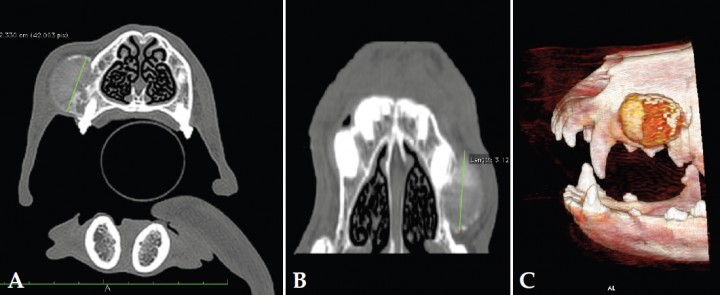

Se remitió el paciente para la realización de un estudio por tomografía computarizada (TAC) craneal y torácica; los hallazgos observados fueron lesión nodular localizada, de 2,3 x 3,1 cm, en el maxilar izquierdo entre el borde caudal del canino hasta el borde craneal del primer molar, con bordes de densidad ósea y una región central de tejido blando que captaba el contraste radiológico de forma marcada, mostrando además inflamación moderada de los tejidos blandos periféricos. A nivel del maxilar se observó una osteolisis de moderada a marcada en las áreas radiculares de los premolares (Fig. 3).

<p>Imágenes de TAC precontraste en ventana de huesos. (A) Plano transversal. (B) Plano dorsal (C) 3D. Se aprecia lesión nodular en la región lateral derecha del hueso maxilar (imágenes cedidas por Diagnosfera).</p>

Imágenes de TAC precontraste en ventana de huesos. (A) Plano transversal. (B) Plano dorsal (C) 3D. Se aprecia lesión nodular en la región lateral derecha del hueso maxilar (imágenes cedidas por Diagnosfera).

En el caso clínico descrito, la realización del TAC prequirúrgico facilitó la planificación operatoria definiendo los límites de la tumoración en las tres dimensiones. En consecuencia se realizó maxilectomía teniendo en cuenta los límites referidos, incidiendo dorsolateral a la sutura nasomaxilar hasta la región palatina de las piezas dentales, incluyendo el margen de una pieza dental sana craneal y otra caudal a la lesión y extirpando la cortical maxilar nasal sin retirar tejido nasal pues, afortunadamente, la tumoración no parecía afectar a la cavidad nasal.